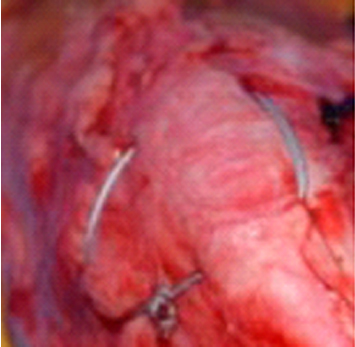

このためによく行われる方法は、Derotational suture(減捻縫合)で対応する方法です。すなわちAntirotational suture(反回旋縫合)である嚢外固定(外側固定)が行われてきました。前十字靭帯断裂の縫合と同じです。いずれの時期に固定が外れますが、その間に固定できれば解決するという論議です。もちろん再度再脱臼する恐れもほんの少しはあるがほとんどは解決します。しかし、この方法は、肢を使用しない時には安定するが、使用した時にはあまり安定しないと言うのが弱点のようです。

この再脱臼の解決のため、最近では膝蓋骨を固定する手技、膝蓋骨支持縫合(Patella sling suture)がより良い方法であろうという推定のもとに、行われ始めつつあります。そして現在の所は良い結果を生んでいるようです。これは大腿骨遠位、尾側(膝蓋骨の尾側)にアンカーを打ち込み、膝蓋骨を前後挟むように縫合糸にてマットレス縫合のように包み、アンカーの穴に通して縫合して固定する方法です。これもあくまでは一時的な固定の目的で行います。またこの方法は、両側に行えば両側性の膝蓋骨脱臼にも適応されます。振り子のように前後には膝蓋骨が動きますが、左右には動きません。この原理は何か種子骨と膝蓋骨の縫合術(Rudy法)と似ているようですが、アンカーを使用する点で違いがあります

▲膝蓋骨支持縫合(Patella sling suture)